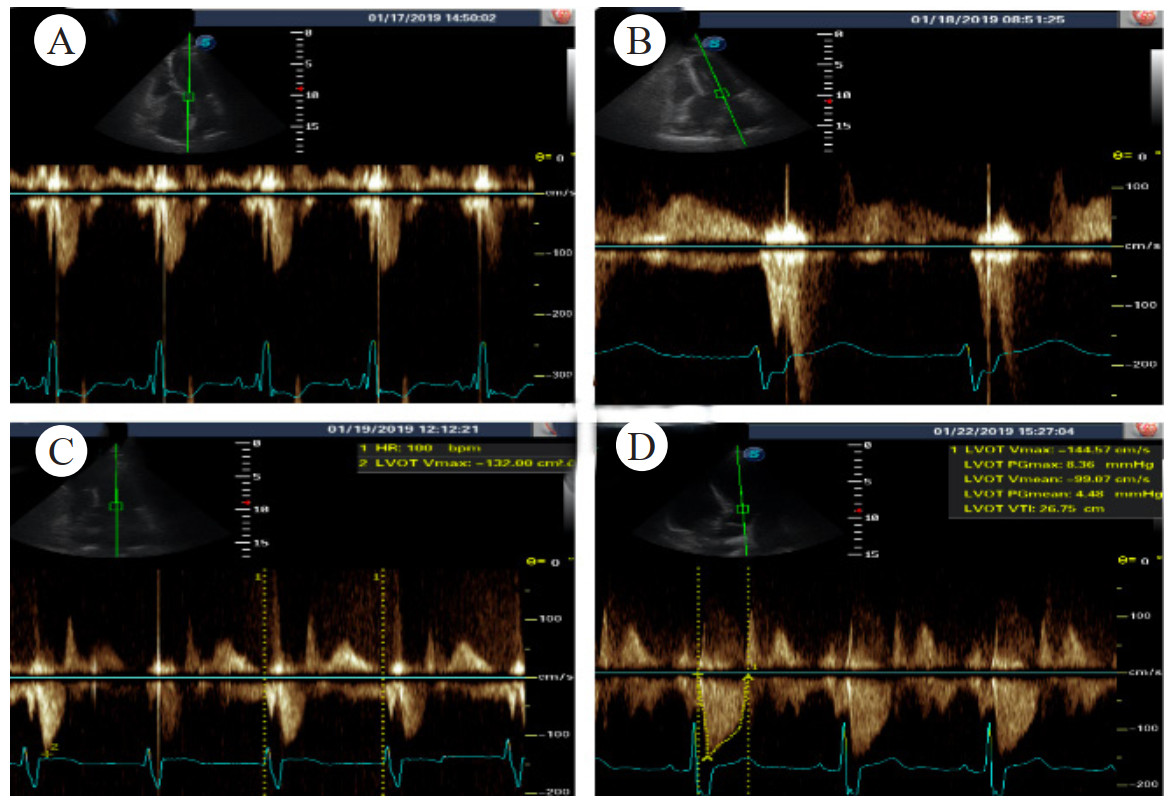

留置脉波指示连续心排血量监测,提示患者心率与心输出量呈反比。患者心率93次/min,每搏量40 mL/次,心输出量3.7 L/min,全身血管阻力指数2 949 dyn/s/cm5/m2,全心舒张末期容积指数1 110 mL/m2。心率升至103次/min,每搏量22 mL/次,心输出量2.3 L/分,全身血管阻力指数5 943 dyn/s/cm5/m2,全心舒张末期容积指数973 mL/m2。患者家属提供病史患者激动后容易晕厥,考虑不能排除左室流出道动态梗阻。行多巴酚丁胺负荷试验,静推2 mg多巴酚丁胺后心率升至155次/min,血压由145/65 mmHg降至65/32 mmHg,左室流出道峰流速由1 m/s增快至约3 m/s,收缩期二尖瓣前叶前移,有典型龙虾爪表现(图 2),符合流出道动态梗阻导致梗阻性休克,加用右美托咪定后患者心率缓慢降至92次/min,血压回升至155/75 mmHg;加用美托洛尔47.5 mg qd、依法布雷定2.5 mg qd鼻饲控制心室率,患者血压稳定并停用去甲肾上腺素;监测左室流出道峰流速波动在1.3~1.4 m/s(图 3)。

| A: 1月17日左室流出道峰流速约1.1 m/s; B: 1月18日多巴酚丁胺后左室流出道峰流速约3 m/s; C、D: 1月19和22日左室流出道峰流速分别1.3 m/s、1.4 m/s 图 2 病例2心脏超声左室流出道峰流速变化 |